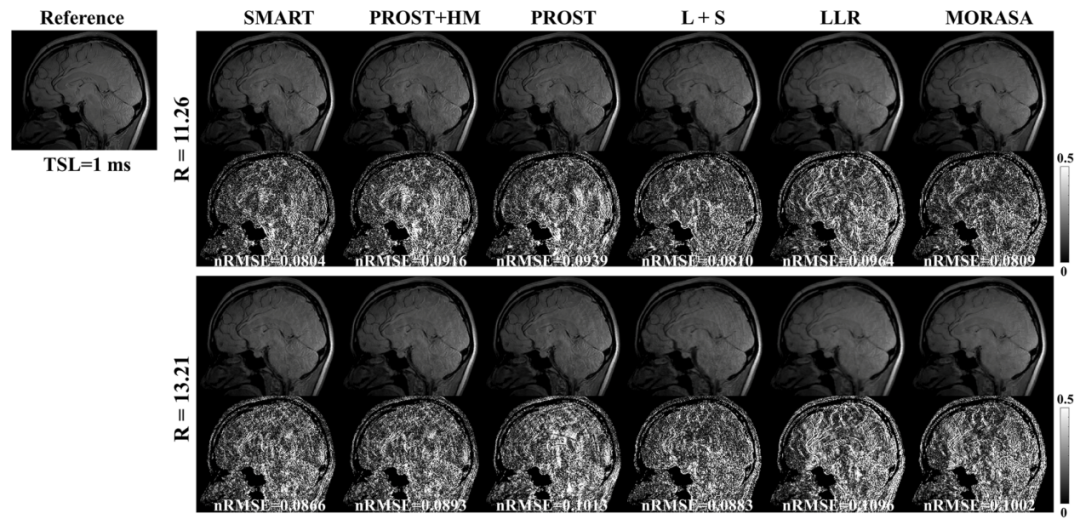

此外,磁共振馳豫值是其重要的物理參數(shù),可以表征組織的一些生理信息,團隊基于該物理弛豫先驗和圖像的結(jié)構(gòu)相似性,提出了基于低秩張量的快速磁共振T1ρ馳豫定量方法(SMART),將掃描時間由全采樣數(shù)據(jù)所需的49.9分鐘縮短至3.8分鐘,且在高達13.2倍加速倍數(shù)下仍能獲得與全采樣數(shù)據(jù)相當?shù)膱D像,且重建誤差小于目前主流的重建方法(圖3)。相關(guān)研究工作發(fā)表在醫(yī)學(xué)成像領(lǐng)域著名期刊IEEE Transactions on Medical Imaging。

圖3.不同加速倍數(shù)下(R=11.26, 13.21)所提的SMART方法與其他主流方法的重建結(jié)果對比。